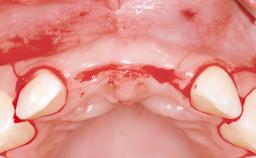

Replacement of Four Incisors with a Fixed Partial Denture on Two Narrow-Neck Implants after Implant Failure

| Bone Augmentation | Horizontal|Staged|Vertical |

| Augmentation Materials | Autogenous block(s)|Xenogenous|Membrane |

| Soft Tissue Anatomy | Intact | Defective | |

| Bone Volume | Horizontally and vertically sufficient | Horizontally deficient | Deficient vertically or deficient vertically AND horizontally |